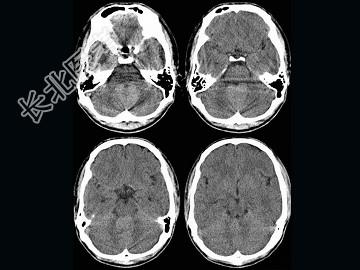

- 单项选择题男,16岁, 头痛、呕吐10天,CT检查, 最可能的诊断为 ( )

A、脑膜瘤

B、髓母细胞瘤

C、室管膜瘤

D、脑血管瘤

E、血管母细胞瘤